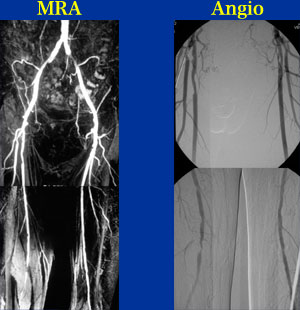

67歳 男性

左間歇性跛行 (300m)

6年前より左間歇的跛行(300m)を自覚。

薬物療法で改善しないため当院紹介受診となった。

ABI 右 0.7  左 0.5

【既往歴】

頚椎症手術(右半身の知覚障害)

開腹胆摘(胆石症)

高血圧(+) 糖尿病(+) 高脂血症(+) 喫煙歴(+)

【治療計画】

左EIA stent

左SFA atherectomy / stent